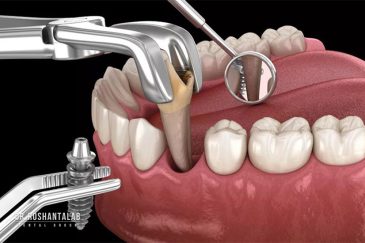

🔸 کاشت دندان یک روزه ( کشیدن و کاشت همزمان )

تجربه کاشت دندان دیجیتال و بدون درد در ۳ دقیقه! استفاده از برترین برندها زیر نظر جراح، با هزینه مناسب و خدمات کامل از کاشت دندان تا روکشارتودنسی دندان